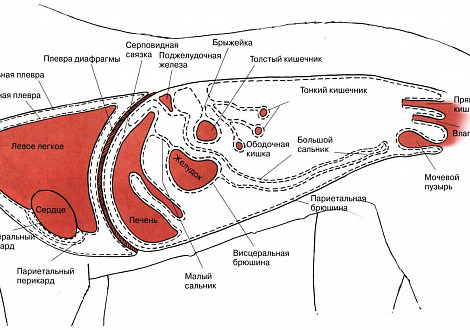

Плевральная полость - это щелевидное пространство между висцеральным и париетальным листками плевры, окружающими каждое легкое. Плевра представляет собой гладкую серозную оболочку. Париетальный или наружный листок плевры выстилают стенки грудной полости и наружные поверхности средостения, покрывают лёгкое и его анатомические структуры (сосуды, бронхи и нервы). В норме плевральные полости содержат незначительное количество серозной жидкости.